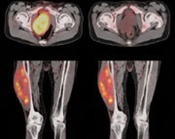

Se usa una amplia gama de técnicas de adquisición de imágenes para poder ver dentro del cuerpo y determinar el alcance de un sarcoma óseo y establecer la presencia o ausencia de enfermedad metastásica distante.

3. TAC contrastado

Pruebas de imágen

Las pruebas de diagnóstico por imágenes utilizan ondas sonoras, rayos X, campos magnéticos o sustancias radiactivas para crear imágenes del interior del cuerpo. Las pruebas de diagnóstico por imágenes pueden realizarse por diversos motivos, como:

Las imágenes más representativas o más comunes son:

3. Tomografía Computarizada

4. PET scan

5. Resonancia Magnética